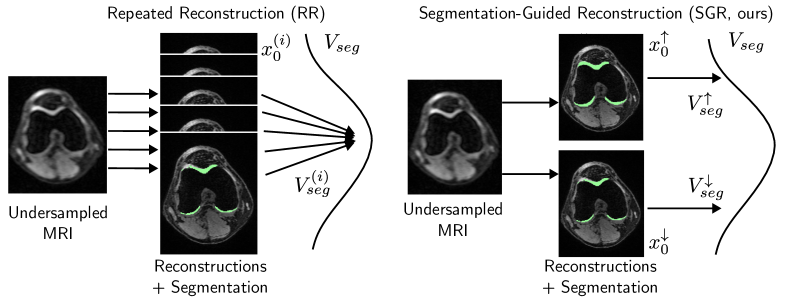

Figure 1: Motivation. Repeated reconstruction tends to create MRI reconstructions that are conceptually similar and not meaningfully diverse. Similar results are also observed in downstream tasks like segmentation in our experiments. Our method in contrast only reconstructs two images, an upper bound (x0superscriptsubscript𝑥0x_{0}^{\uparrow}) and a lower bound (x0superscriptsubscript𝑥0x_{0}^{\downarrow}) reconstruction, corresponding to an upper (Vsegsuperscriptsubscript𝑉𝑠𝑒𝑔V_{seg}^{\uparrow}) and lower bound (Vsegsuperscriptsubscript𝑉𝑠𝑒𝑔V_{seg}^{\downarrow}) on the segmentation volume, giving an intuitive understanding of the segmentation uncertainty.

In this paper, instead of random sampling, we propose to reconstruct two MRI-images per segmentation class corresponding to the upper and lower bound segmentation volume. To this end, we introduce a novel method called Segmentation Guided Reconstruction (SGR). SGR builds on DM-based MRI reconstruction. However, rather than standard sampling, we guide the reconstruction process with the gradient of segmentation losses that either penalize small segmentation volumes or large segmentation volumes. The resulting lower and upper bound reconstructions and segmentations are an intuitive way of understanding the segmentation uncertainty which arises due to the ill-posed nature of the reconstruction problem. See Fig. 1 for a visual explanation of the motivation. In summary, our contributions are: